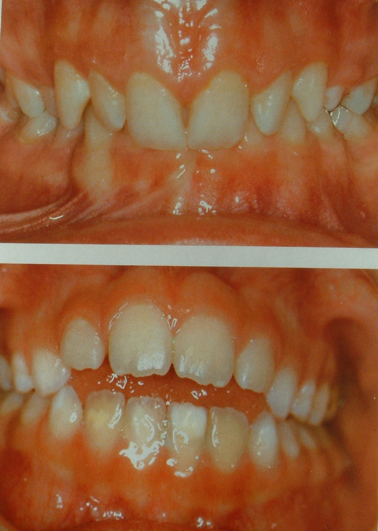

3.2.1 Alterazioni sul piano frontale

Morso aperto

E’ presente molto spazio verticale fra i denti anteriori superiori e inferiori. Oltre al fatto di perdere il sigillo delle labbra, in questi casi si instaura anche una deglutizione, detta infantile, con la lingua che spinge violentemente fra le due arcate, probabilmente per cercare di ottenere quella chiusura che permetta una depressione utile alla deglutizione. Le principali cause di del morso aperto sono il ciuccio e il dito in bocca.

Morso coperto

gli incisivi superiori coprono eccessivamente quelli inferiori, a volte completamente. Se gli incisivi superiori sono flessi anteriormente creando così uno spazio trasversale eccessivo tra loro e gli incisivi inferiori (overjet), questa situazione fa perdere la chiusura delle labbra (sigillo labiale) e obbliga la lingua ad un lavoro anomalo a ogni deglutizione di saliva. Se gli incisivi superiori sono piegati posteriormente, ciò può condizionare i momenti della mandibola costringendola a stare più indietro.